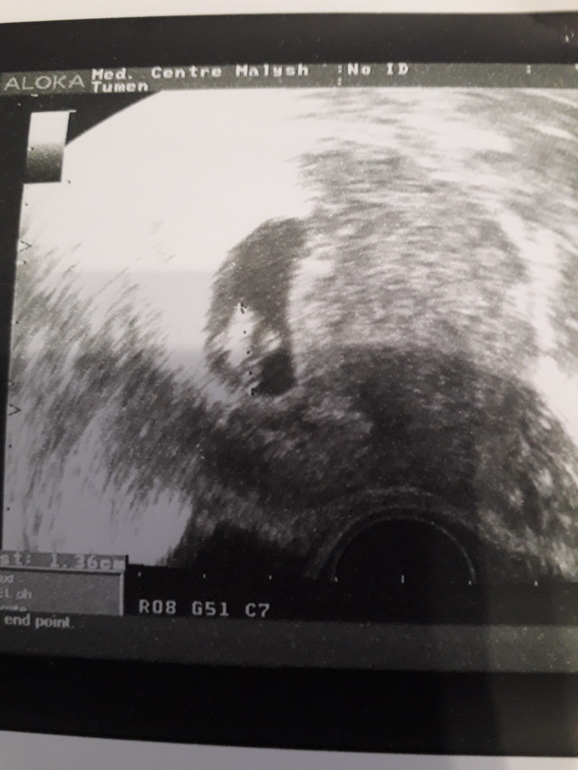

УЗИ 7 неделек

Я БЕРЕМЕННА !Дождалась, наконец-то УЗИ с сердечками. Все хорошо у нас, малыш один, в матке, 1.36. Моя врач мягко так намекнула, что вроде бы снова мальчик. Она знает, что 2 у меня уже есть. Да не, так рано, что там увидишь?!